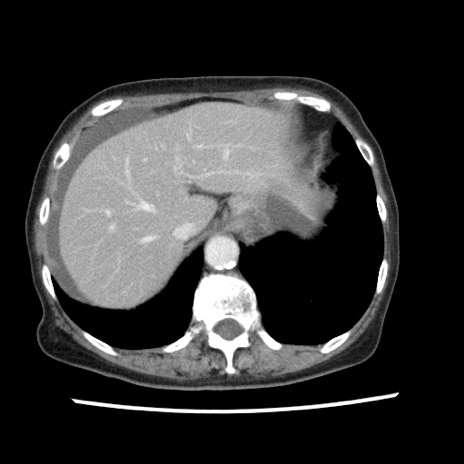

冠状断像

【症例】80歳代女性

【主訴】腹痛

【現病歴】8時間前から腹痛あり来院。

【既往歴】糖尿病、脂質異常症、子宮体癌にて子宮全摘術

【身体所見】意識清明・会話良好だが腹痛で苦悶様、全腹部にわたって反跳痛と圧痛あり

【データ】WBC 13600、CRP 0.14、LDH 224、CK 90